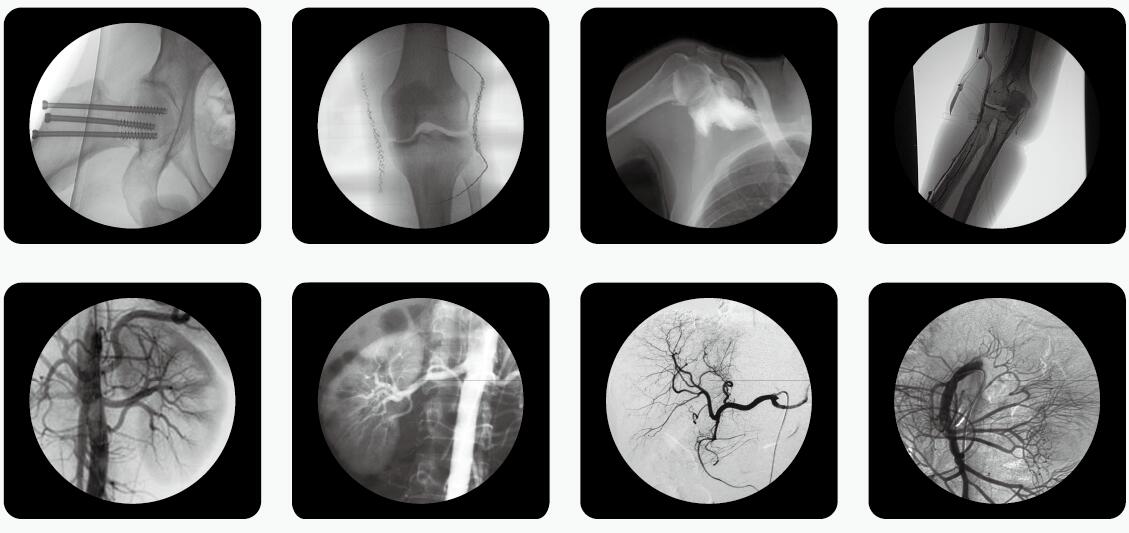

通过X光检查,临床医生可以获取病人很多重要的,甚至性命攸关的医疗信息,比如肺 炎、骨折、肠梗阻等。这些普通X光检查,对平常人而言就像是拍数码照相,咔,可以了。但是对孕妇而言,有时的确是一个艰难的决策。

其实,绝大部分X光检查http://www.pl999.com/newsinfor.php?id=25608&newsclass=1的部位都是四肢、头、牙齿或者胸部,孕妇的生殖腺并没有直接暴露在X光下。因此,在这些情况下,只要合理曝光及防护,对胎儿是没有危害和影响的。

但是,如果孕妇需要做腹部、盆腔、腰椎等X光检查,此时胎儿是直接暴露在X光下的,这种情况就需要与医生探讨X光检查的利弊后再做决定。